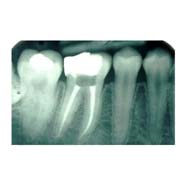

Root Canal Treatment (RCT) A tooth has three layers enamel, dentin and pulp. When the cavity is so deep that it reached the pulp, RCT has to be done.

In this all the infection from within the tooth is removed, all the canals in the root are cleaned and medicament is placed. The tooth is sealed so that no infection seeps in after RCT.

After performing RCT, the tooth becomes weak and brittle. That’s why post RCT crown is very important to protect the tooth.

Placing a crown helps the tooth to be strong and capable of withstanding the forces as in the normal tooth.

Root Canal inclusive of crown can be completed within 2 to 3 sittings.

What is the success rate of Rct? Root canal has a success rate of more than 95% thanks to the advanced materials available to perform the procedures today such as Apex locators and digital xrays to ensure accuracy; rotary instruments and fiber posts with core build up materials to improve the strength of tooth and CAD-CAM precision crowns bonded chemically to the tooth.